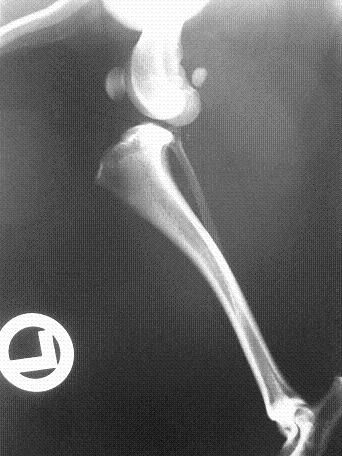

Die Röntgenaufnahme zeigt, wie die Oberschenkelgelenksfläche regelrecht hinter der des Unterschenkels positioniert ist (Dislokation). Die Gelenksfläche des Unterschenkels ist sehr steil. Nach dem Riss des vorderen Kreuzbandes wird der Gewichtskraft und Beschleunigungsenergie nichts mehr entgegengehalten. Das Ausgleiten der Oberschenkelgelenksfläche über den Meniskus verursacht meist starke Schmerzen und Lahmheit. In diesem Bild ist die Oberschenkelgelenksfläche regelrecht verlagert. Gerade bei den kleineren Hunden beobachten wir oft sehr steile Gelenksflächen. Unbehandelt sehen wir desöftern Hunde, die dieses Gelenk nicht mehr beugen können, weil die Sehnen und Bänder sich nach der Dislokation verkürzt haben.